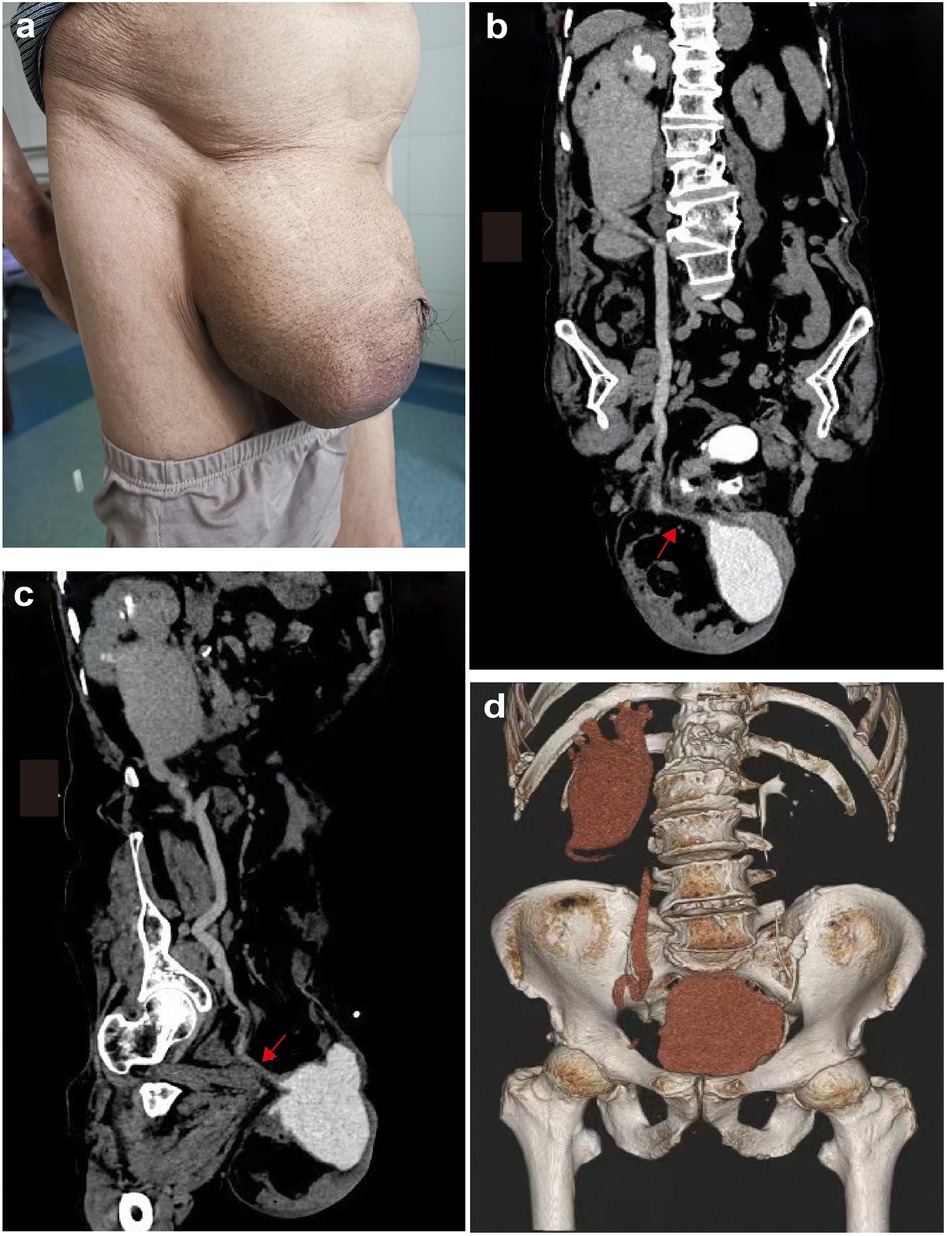

Inguinal hernia repair is a routine operation. However, it is rare for the organs of the urinary system to prolapse as the contents of the hernia. An 80-year-old obese male with a history of three prior open inguinal hernia repairs presented with a recurrent large scrotal mass and severe right hydronephrosis. Preoperative Computed Tomography urography (CTU) revealed a giant inguinal vesicoureteral hernia involving the bladder and ureter. The patient underwent transabdominal preperitoneal repair (TAPP) with intraoperative identification of herniated bladder-ureter components facilitated by bladder catheter saline infusion and ureteroscopic assistance. Postoperative CTU at 1 week demonstrated complete reduction of herniated viscera and resolution of hydronephrosis. No complications occurred, and 6-month follow-up confirmed sustained recovery without recurrence. This case provides valuable insight into preoperative diagnostic difficulties and the intra-and postoperative management of an inguinal vesicoureteral hernia in a multiple relapsed old man, highlighting the importance of accurate diagnosis and appropriate surgical intervention in the treatment of this disease.